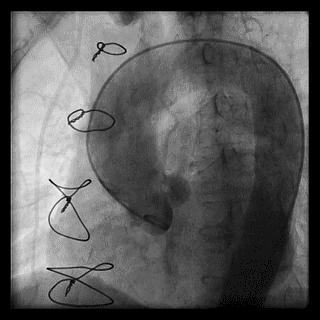

2014年,Patel T等首先采用球囊辅助通过技术(Balloon-assisted tracking,BAT),用于通过桡动脉途径中扭曲、细小节段(包括严重痉挛节段)(图1-2)。

图2 BAT技术应用实例1。52岁女性患者冠脉严重痉挛(A),注射2次鸡尾酒后仍未缓解(B),采用BAT技术(C),顺利介导7F指引导管通过桡动脉严重痉挛节段(D)